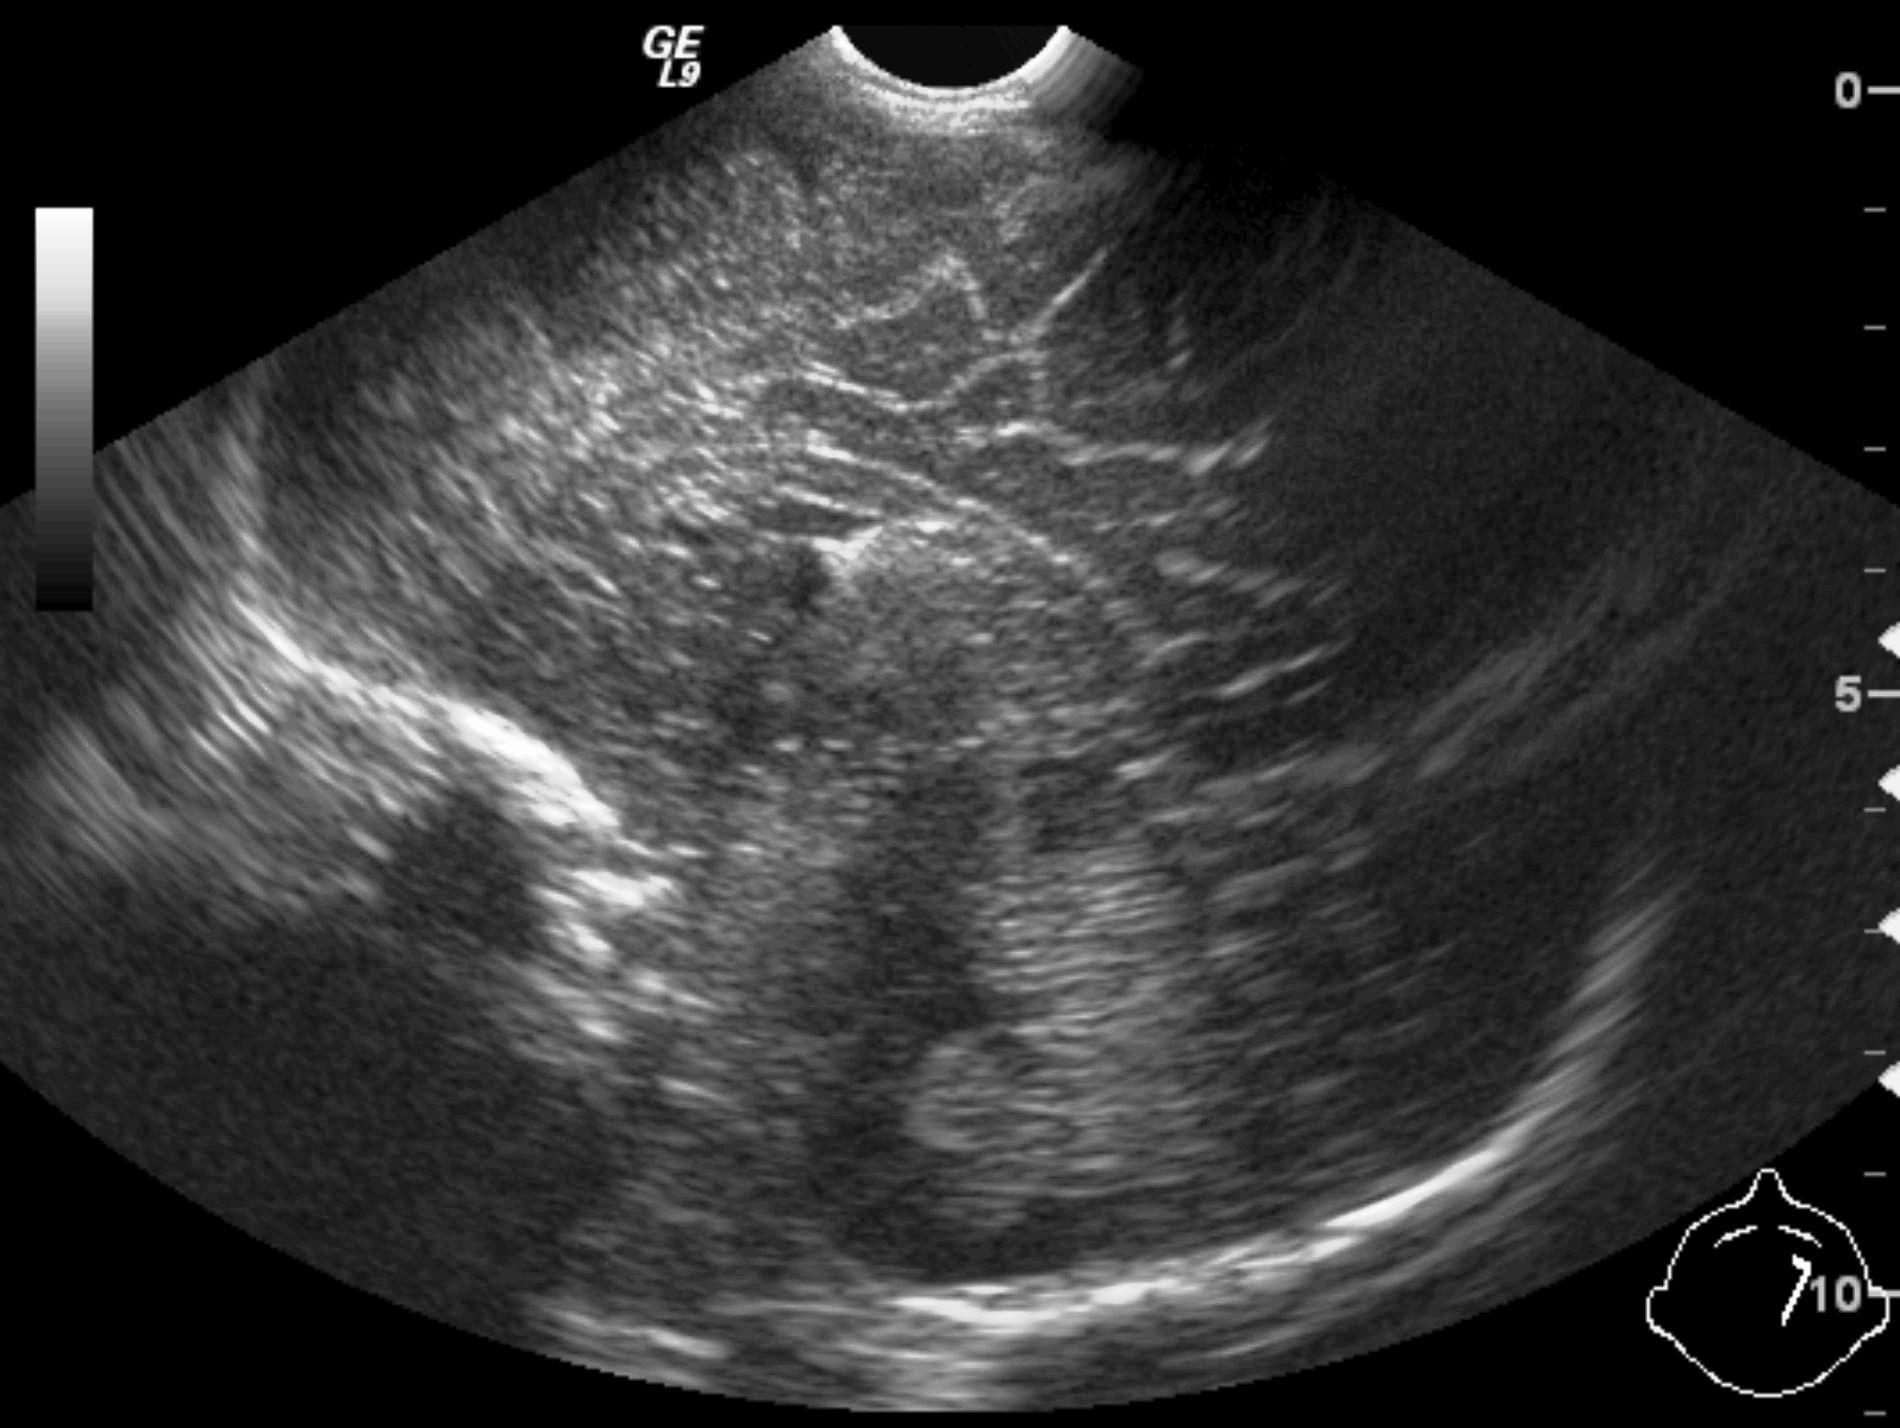

Invagination. A distal intestinal loop invaginating to a proximal intestinal loop can result in a mechanical intestinal obstruction, and cause ischemic damage. It most frequently occurs in infants (3-24 months) with recurring, colic-like complaints, distended intestines, a palpable mass and with frequent vomiting and bloody stool. Invagination requires immediate diagnosis and desinvagination. US exam reveals the invaginated intestines as a “target” sign in axial cross section and looks like a “pseudokidney” in longitudinal cross section. The therapy is hydrostatic or pneumatic desinvagination. Perforation and/or peritonitis are absolute contraindications to these procedures. Hydrostatic desinvagination can be performed under fluoroscopy or with US guidance and is considered successful if air or the contrast material appears in the terminal ileum and the invaginated loop disappears. If these efforts do not succeed, surgical desinvagination is needed.

17. “Target” sign. Invagination. .